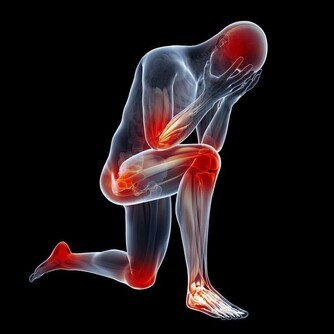

治療肩膀與頸部痠痛的方法

1. 熱敷與冷敷

- 熱敷(40-50°C,15-20分鐘):促進血液循環,放鬆緊繃的肌肉,適用於長期痠痛或疲勞造成的不適。

- 冷敷(冰敷10-15分鐘):有助於減少急性發炎與腫脹,適用於運動後或突發性疼痛。

2. 按摩與物理治療

- 按摩能夠幫助放鬆緊繃的肌肉,提升血液循環。

- 物理治療可透過電療、超音波治療或徒手治療來改善頸肩部位的活動度。

3. 針灸與中醫治療

針灸透過刺激特定穴位,可幫助舒緩肌肉緊繃與改善血液循環。中醫推拿或拔罐也可促進氣血流動,減輕疼痛感。

4. 服用消炎止痛藥

若疼痛影響日常生活,可適量服用 非類固醇消炎藥(NSAIDs),如布洛芬(Ibuprofen),來減少發炎與疼痛,但不宜長期依賴,應諮詢醫師意見。

5. 就醫診斷與專業治療

若肩頸疼痛長期無法緩解,甚至影響日常生活,如手部麻木、頭暈、活動受限等症狀,應立即就醫,透過 X 光、MRI 或神經檢查 確定病因,接受適當治療。